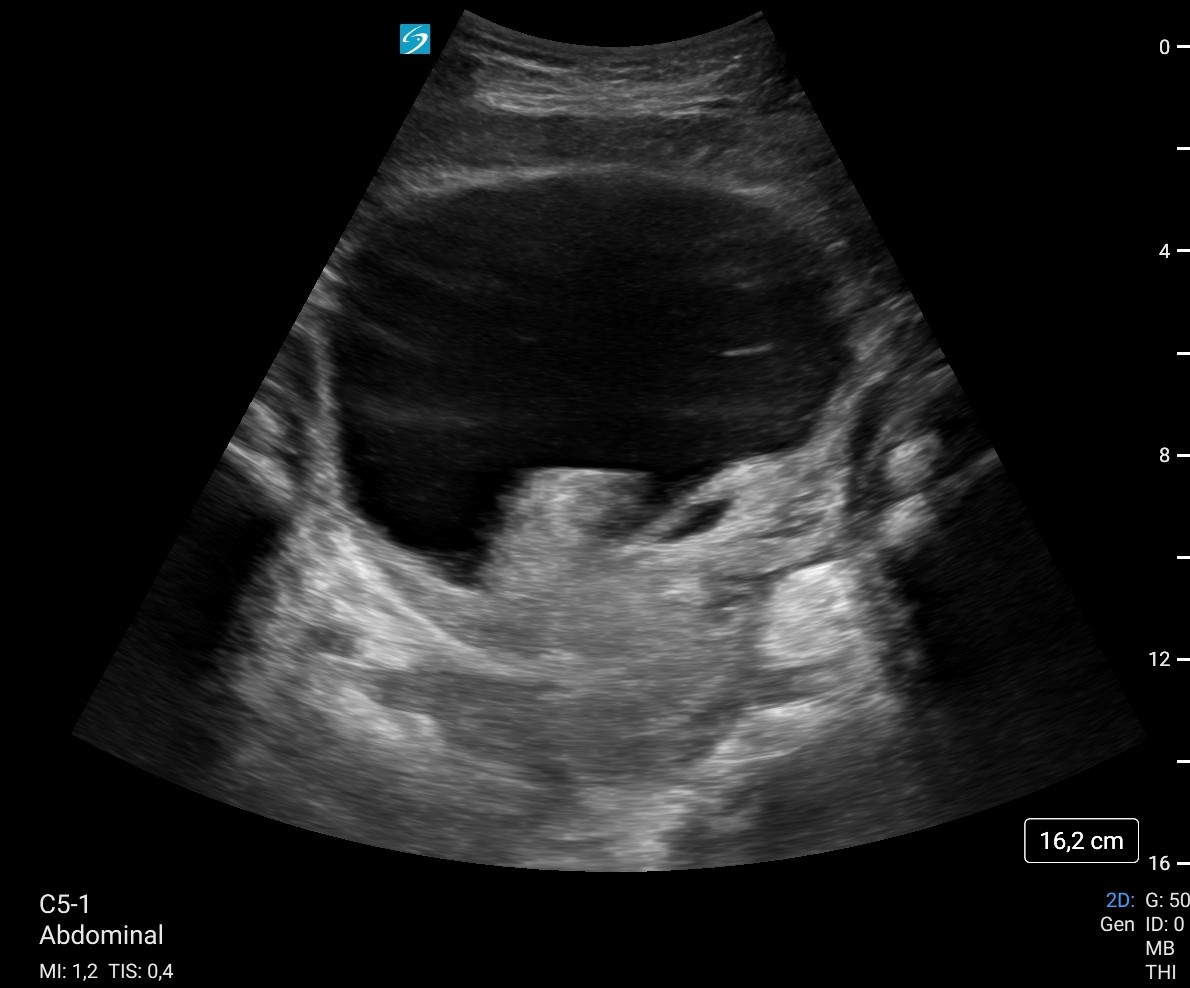

Ecografía a pie de cama: Vejiga 700 cc con imagen hiperecogénico intravesical, irregular, pensando en coágulo como primera opción sin poder descartar tm vesical. Sospecha de retención aguda de orina (RAO) con probables de coágulos intravesicales vs posible tumor vesical.

Hallazgos ecográficos

Ecografía reglada a la mañana siguiente:

Vejiga urinaria a máxima repleción, identificando contenido hiperecoico de morfología tubular en pared lateral inferior izquierda, parece desplazarse a los meatos con los cambios posicionales, lo que sugiere existencia de coágulos como primera posibilidad, sin poder descartar tumor subyacente. Se recomienda valoración con cistoscopia, lavados vesicales...